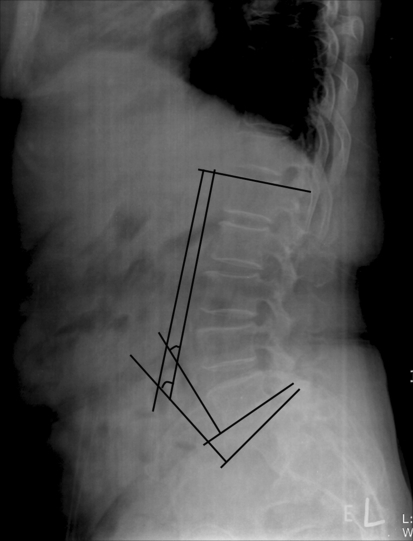

TRALL method (Fig. 4).

Fig. 4.

The largest perpendicular distance to the posterior longitudinal ligament from a line connecting the posterior–inferior of S1 and the superior–posterior body corner of L1 was used to locate the lumbar curve apex. This apex point was used as the vertex of the angle with the sides to L1 and S1. (TRALL method)

The largest perpendicular distance to the posterior longitudinal ligament from a line connecting the posterior–inferior of S1 and the superior–posterior body corner of L1, was used to locate the lumbar curve apex. This apex point was used for the vertex of the angle with the L1 and S1 sides [5].